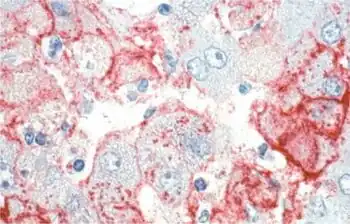

Lassa virus (Arenaviridae)

Lymphocytic choriomeningitis virus (Arenaviridae)

Hantavirus (Hantaviridae)

_EM_PHIL_2175_lores.jpg.webp)

Vesicular stomatitis virus (Rhabdoviridae)